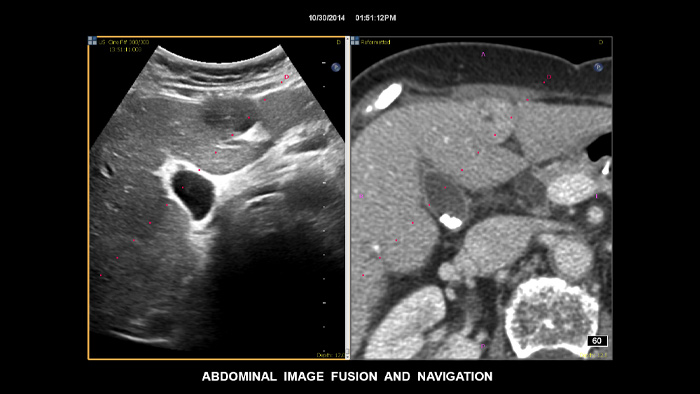

Tome decisões confiantes, mesmo em casos de diagnóstico tecnicamente difíceis, com as capacidades de fusão de imagens e navegação da agulha da Philips. O fluxo de trabalho otimizado permite aos médicos obter uma fusão rápida e eficaz de TAC/RM/PET com a ecografia em tempo real, enquanto a navegação da agulha ajuda a orientar a biópsia de lesões pequenas e de difícil acesso2.

Utilizando o contorno tumoral, os utilizadores podem planear e direcionar lesões com uma ferramenta semiautomatizada que ajuda a delinear um contorno 3D à volta de uma estrutura de interesse, melhorando potencialmente a orientação do procedimento com casos tecnicamente difíceis onde a lesão pode não ser facilmente visualizada.